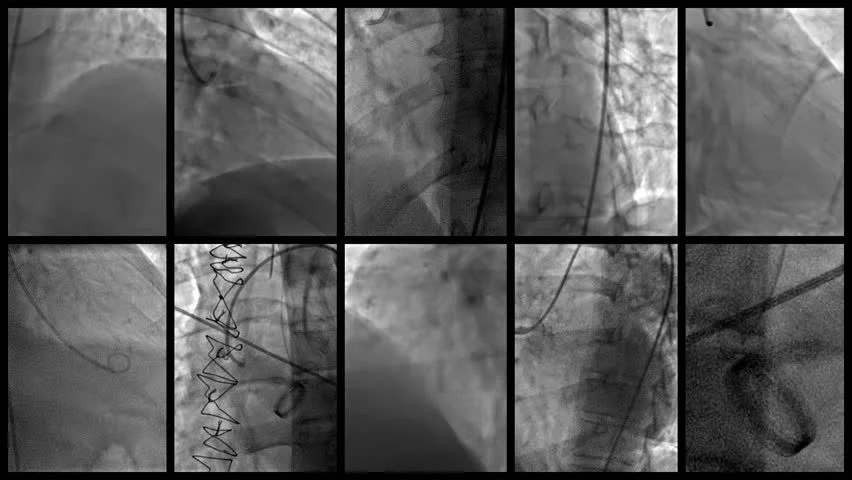

آنژیوگرافی قلب، که گاهی به عنوان کاتتریزاسیون قلبی یا عکس‌برداری عروق کرونری شناخته می‌شود، یک روش تشخیصی پیشرفته است. در این پروسه، پزشکان با استفاده از یک لوله نازک و انعطاف‌پذیر به نام کاتتر، ماده کنتراست (رنگ خاصی) را به شریان‌های قلب تزریق می‌کنند و با اشعه ایکس، جریان خون را مشاهده می‌کنند. این روش، استاندارد طلایی برای بررسی بیماری شریان کرونری (CAD) است و به پزشکان اجازه می‌دهد تا انسدادها یا تنگی‌های عروق را با دقت ببینند.

این تکنیک تهاجمی اما ایمن، معمولاً در آزمایشگاه کاتتریزاسیون یا اتاق اشعه ایکس انجام می‌شود. تیمی متشکل از متخصص قلب (کاردیولوژیست)، پرستار، تکنسین قلبی و رادیوگرافر، این کار را با دقت بالا پیش می‌برند. بر اساس اطلاعات معتبر از Mount Sinai، آنژیوگرافی قلب نه تنها ساختار عروق را نشان می‌دهد، بلکه عملکرد دریچه‌ها، فشارهای داخل قلب و حتی سطوح اکسیژن را ارزیابی می‌کند. اگر احساس می‌کنید قلب‌تان در حال فریاد زدن است، این روش می‌تواند سکوت لازم برای تشخیص را فراهم کند.

آنژیوگرافی قلب معمولاً ۳۰ تا ۶۰ دقیقه طول می‌کشد و تحت بی‌حسی موضعی انجام می‌شود. ابتدا، آرام‌بخشی ملایمی برای کاهش اضطراب داده می‌شود. محل ورود کاتتر – اغلب کشاله ران یا مچ دست – تمیز و بی‌حس می‌شود. سپس، کاتتر از طریق شریان وارد شده و با هدایت اشعه ایکس به قلب می‌رسد.

وقتی کاتتر در جای خود قرار گرفت، ماده کنتراست تزریق می‌شود. ممکن است احساس گرمای موقت یا طعم فلزی کنید – این طبیعی است و پزشکان هشدار می‌دهند. تصاویر فلوروسکوپی (توالی سریع اشعه ایکس) گرفته می‌شود تا انسدادها مشخص شوند. در پایان، کاتتر خارج شده و فشار به محل اعمال می‌شود. این مراحل، مانند یک رقص دقیق، قلب‌تان را بدون آسیب بررسی می‌کنند.

مرحله ۳: تزریق ماده حاجب

زمانی که کاتتر در جای مناسب قرار گرفت، ماده حاجب تزریق می‌شود. این ماده باعث می‌شود تصاویر واضحی از عروق کرونری با اشعه ایکس گرفته شود.

مرحله ۴: تصویربرداری

پزشک با استفاده از دستگاه مخصوص، جریان ماده حاجب در عروق را مشاهده و ضبط می‌کند. این تصاویر محل دقیق انسداد را مشخص می‌کنند.